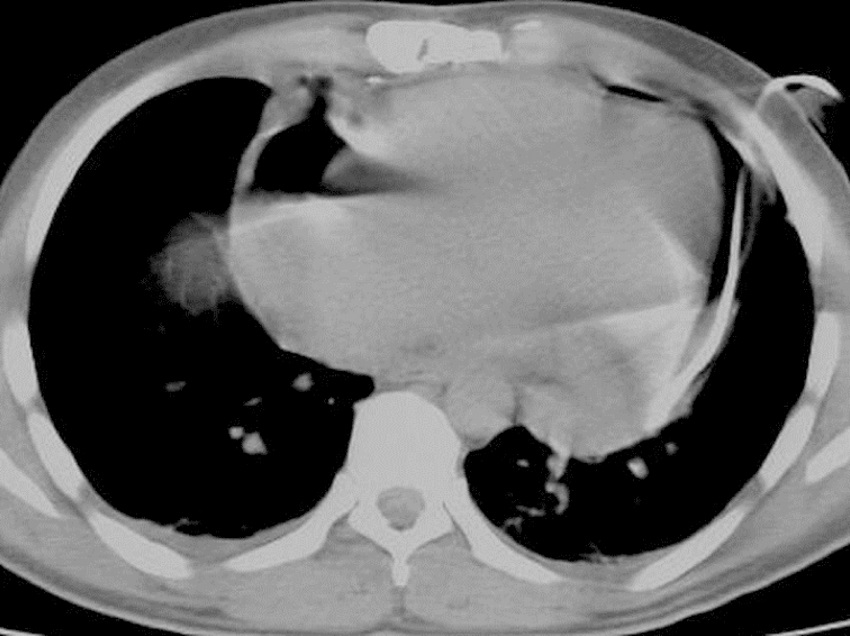

Having been colored and disinfected, the marked area was covered with sterile drapes. As a local anesthetic agent, 2% lidocaine was used. Then, an 18 G needle with negative puncture was entered to the pericardial cavity, the needle was fixed at the level of liquid aspiration, and the CT was taken again to reaffirm the needle's position (Figure 2). After confirming that it was in the intrapericardial space, the liquid was aspirated and evaluated. If hemorrhagic characteristics were thought to be possible after confirming that the blood defibrinated, a 0.035" guidewire was sent to the pericardial cavity through the needle (Figure 3). The needle was removed and the CT was taken; after confirming that the guidewire was in the intrapericardial cavity, an 8 or 10 F nephrostomy catheter was advanced into the pericardial cavity through a catheter guide. A three-way tap was installed in the tip of the catheter and the liquid was poured into a 50 ml syringe. The catheter was identified and it was connected to the closed underwater drainage system (Figure 4).